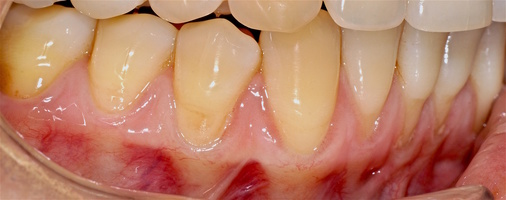

В марте 2017 года в клинику обратилась пациентка Ч., 28 лет (табл. 1) без вредных привычек, с положительным социальным статусом, астенического телосложения. С жалобами на тотальное обнажение корней зубов с повышением чувствительности от термических раздражителей, эстетические дефекты, абразии твердых тканей зубов.

Исходный объем мягкотканного комплекса атрофичен, тонкий биотип десны. Мелкое преддверие полости рта на нижней челюсти в переднем отделе, от 44-го до 34-го зубов высокое прикрепление слизисто-мышечных тяжей.

В области от 1.6 до 2.6 и от 3.6 до 4.6 все зубы имеют некариозные поражения разной степени, такие как эрозии эмали и клиновидные дефекты, вовлекающие в процесс ткани эмали и дентина. Подвижности зубов не выявлено (рис. 1а-е) [9].

Исходный диагноз: генерализованные рецессии десны 1 и 2 класса по Миллеру [7, 9, 10].